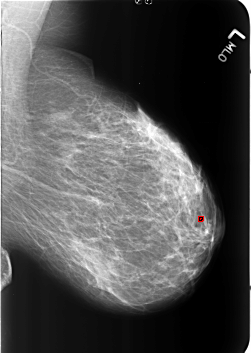

B_3213_1.LEFT_MLO

FILE: B_3213_1.LEFT_MLO.OVERLAY

TOTAL_ABNORMALITIES 1

ABNORMALITY 1

LESION_TYPE CALCIFICATION TYPE LUCENT_CENTER DISTRIBUTION N/A

ASSESSMENT 2

SUBTLETY 5

PATHOLOGY BENIGN_WITHOUT_CALLBACK

TOTAL_OUTLINES 1

BOUNDARY